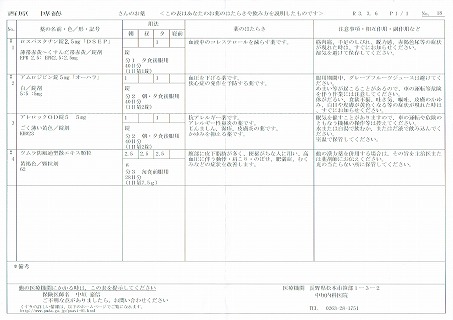

2021.11.13より 西原クリニック 0968-62-0622

2024.7.12(金) 2回目のコロナ感染 7.16(火)検査で陽性

2024.4.13 オロパタジンに戻る

2024.3.9 鼻炎と目のかゆみがひどく、オロパタジン⇒デザレックス&点眼薬 アレジオン に変更 2.10 血液検査結果

2023.11.13 ウイルス性の風邪と診断 熱の最大は13日夜 37.1℃

23.04.18 コロナ陽性

22.10.29 鼻炎薬吸引 モメタゾン点鼻液50μg 噴霧用 5mg10g 杏林 56噴霧用

22.09.10

2022.02.19

2021.12.04 西原クリニック処方箋=pdf

2021.11.13

2021.04.24 2021.03.06 中垣医院処方箋 =PDF